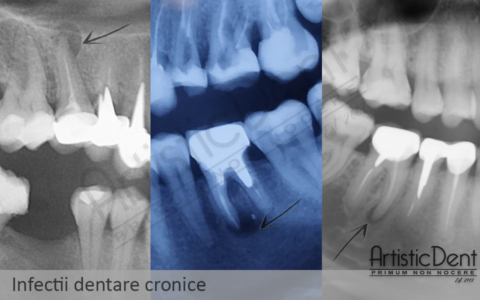

4.Durerea dentara aparuta doar la mestecarea unor alimente tari sau senzatia de dinte inalt, sugereaza prezenta unui proces infectios dentar cronic, care se va reacutiza.